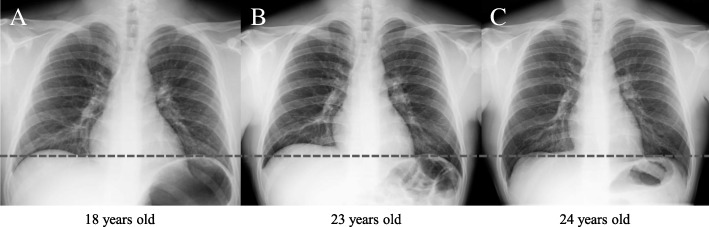

Fig. 3.

Changes in the diaphragm position on chest x-rays. The horizontal dotted line indicates the left diaphragm position. b A slight elevation of the right diaphragm can be observed relative to its position in (a). c Chest x-ray obtained after normalization of the serum homocysteine level illustrating the right diaphragm in a lower position than in (b)

Upon admission to our hospital due to a tonic seizure at the age of 23, the patient underwent a detailed examination. He had no gingival overgrowth but did have macrocytosis without anemia (hemoglobin, 16.8 g/dl; MCV, 102.8 fl). We observed mild elevation of the partial pressure of carbon dioxide (PCO2) and bicarbonate without acidemia in the venous blood, suggesting chronic CO2 retention (pH, 7.386; PCO2, 50.9 mmHg; bicarbonate, 29.2 mmol/L). The blood concentrations of all AEDs were within the relevant therapeutic ranges (phenytoin, 13.35 μg/ml [therapeutic range, 10–20 μg/ml]; phenobarbital, 20.81 μg/ml [10–35 μg/ml]; levetiracetam, 15.8 μg/ml [12–46 μg/ml]). The patient’s serum levels of folate, riboflavin, and pyridoxal decreased to below-normal ranges, and his cobalamin level decreased to the lower limit of the normal range (folate, 1.6 ng/ml [normal range, 3.6–12.9 ng/ml]; riboflavin, 3.6 μg/dl [12.8–27.6 μg/dl]; pyridoxal, 3.9 ng/ml [6.0–40.0 ng/ml]; cobalamin, 275 pg/ml [233–914 pg/ml]). Plasma amino acid analysis revealed a decrease in the methionine level and a marked elevation in the plasma homocysteine level, whereas other essential amino acids were within normal ranges (methionine, 15.2 μmol/L [18.9–40.5 μmol/L]; homocysteine, 202 μmol/L [5.0–15.0 μmol/L]). Urine organic acid analysis revealed no abnormal findings, including methylmalonic acid. A chest x-ray demonstrated a slight elevation of the right diaphragm relative to the findings of a previous x-ray (Fig. 3a, b). Brain magnetic resonance imaging revealed no abnormalities. Genetic analysis identified three homozygous polymorphisms in the MTHFR gene (NM_005957.4): c.665C>T (p.Ala222Val; also known as C677T), c.1166 + 31C>T, and c.1305C>T (p.Phe435=). Supplementation with folic acid (15 mg/day), pyridoxal phosphate (30 mg/day), and methylcobalamin (1.5 mg/day) was started, and phenytoin and phenobarbital were switched to lamotrigine. Thereafter, the patient’s MCV decreased to < 100 fl, and his methionine level was normalized to the vitamin levels. PCO2 and bicarbonate levels in the venous blood continued to decrease, which was accompanied by a normalization of the diaphragm position (Figs. 2 and 3c). The patient’s auditory hallucinations, multiple personalities, lethargy, and other neuropsychological symptoms improved as serum homocysteine levels were reduced to within normal ranges with supplementation. However, his seizure attacks still occurred once per month.

The patient had mildly increased CO2 levels and slight elevation of the right diaphragm, which improved with normalization of serum homocysteine levels. Neonates and young infants with severe MTHFR deficiency often present with respiratory complications such as apnea and phrenic nerve palsy [2, 25]. Although the precise mechanism of these respiratory complications remains poorly understood, it has been presumed to result from central and peripheral neurological impairment; this can be attributed to SAM deficiency, which is involved in dysmyelination [4, 26]. To our knowledge, no clinical studies have documented MTHFR C677T-related respiratory symptoms. C677T-associated hyperhomocysteinemia should be considered as a differential diagnosis in patients presenting with respiratory symptoms during AED therapy.